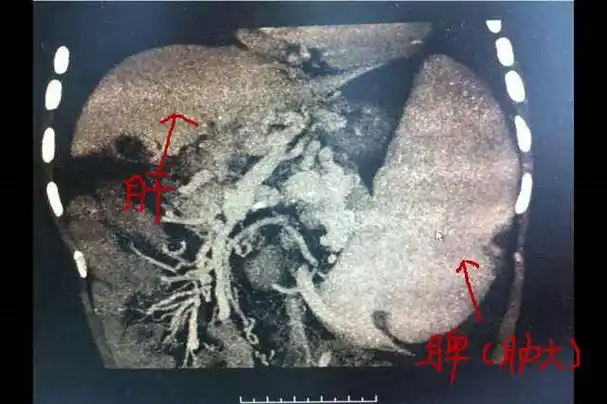

大 上图:正常人脾脏影像学表现 下图:脾脏肿大影像学表现